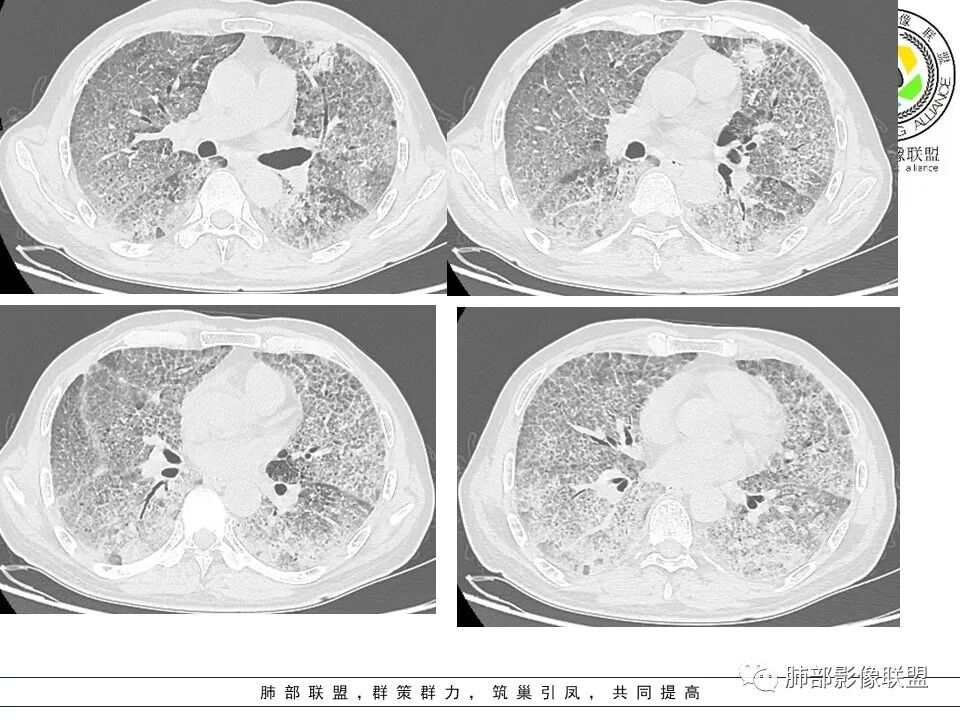

八爪:弥漫分布磨玻璃密度影,小叶间隔增厚,典型铺路石征,考虑PAP伴发感染性病变,鉴别特发性间质性肺炎,弥漫性腺癌,建议支气管灌洗;左肺上叶舌段不规则团片状阴影,显示不清,密切随访

小谢:慢性病程,无发热,双肺弥漫性病变,GGO,铺路石征,首先考虑PAP,鉴别肺腺癌

一米阳光:中老年男性,病程长。双肺弥漫性ggo,小叶间隔明显增厚,铺路石样改变,考虑PAP,鉴别pcp。建议支气管镜检查并灌洗。病史有尘肺接触史,排除尘肺合并结核

我心飞翔:中年男性,双肺弥漫磨玻璃影,铺路石征,病灶内可见扩张支气管,CEA高,血象高,黄痰,考虑PAP并感染,腺癌待排

郑氏刀刀:双肺弥漫性磨玻璃影,伴铺路石征,下叶为主,且见斑片实变影,白细胞高,结合执业史,尘肺,PAP伴感染,腺癌待排。

小赵:中老年男性患者。慢性病程,多次咳黄痰,治疗效果一般,反复发生。CT表现为双肺弥漫磨玻璃样改变,并呈细网格样铺路石状改变,上下肺无明显差异。双下肺为主多发渗出实变,边界不清,抗炎治疗后病变吸收不明显,局部似有进展。考虑肺泡蛋白沉积症基础上合并感染。肿瘤标志物高,中老年患者,肺炎型肺癌不除外。

南边:只有GGO+网格(小叶间隔增厚),然后就是分布的问题

1、GGO+网格——碎石路征

2、分布无特定位置,较随机

3、可有少许实变——部分与层厚有关

4、小叶间隔内静脉增粗

5、病灶较多时部分可见重力趋势

1.由于脂蛋白的沉积和占据,肺泡腔含气量减少,这是影像上较大范围“磨玻璃影”的基础。

2.由液体、细胞浸润和纤维组织造成的小叶间隔增厚是影像上多边形“铺路石征”的基础。

3.显眼的小叶间隔对病灶有阻挡作用是形成影像上“地图样改变”的基础。我们观察到的病灶与临近相对正常肺组织之间常常有比较清楚的分界。

这种表现颇具特征性。但有部分患者(1/4)仅有磨玻璃影而未显示小叶间隔增厚,这种情形我们很难将PAP列为第一诊断。

4.病灶常多发,但心尖区及膈角区相对轻微。